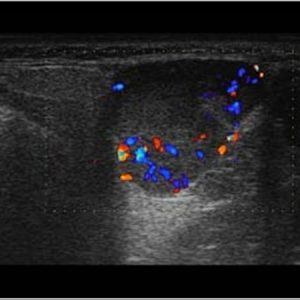

U tuyến nước bọt

Lượt xem: 170» 17-01-2021 -

U tuyến nước bọt

Lượt xem: 174» 17-01-2021 -

U tuyến nước bọt

Lượt xem: 149» 17-01-2021 -

U tuyến nước bọt

Lượt xem: 147» 17-01-2021 -

U tuyến nước bọt

Lượt xem: 146» 17-01-2021 -

U tuyến nước bọt

Lượt xem: 151» 17-01-2021 -

U tuyến nước bọt

Lượt xem: 146» 17-01-2021 -

U tuyến nước bọt

Lượt xem: 136» 17-01-2021 -

U tuyến nước bọt

Lượt xem: 132» 17-01-2021 -

U tuyến nước bọt

Lượt xem: 209» 17-01-2021 -

U tuyến nước bọt

Lượt xem: 150» 17-01-2021 -

U tuyến nước bọt

Lượt xem: 185» 17-01-2021 -

U tuyến nước bọt

Lượt xem: 151» 17-01-2021 -

U tuyến nước bọt

Lượt xem: 212» 17-01-2021 -